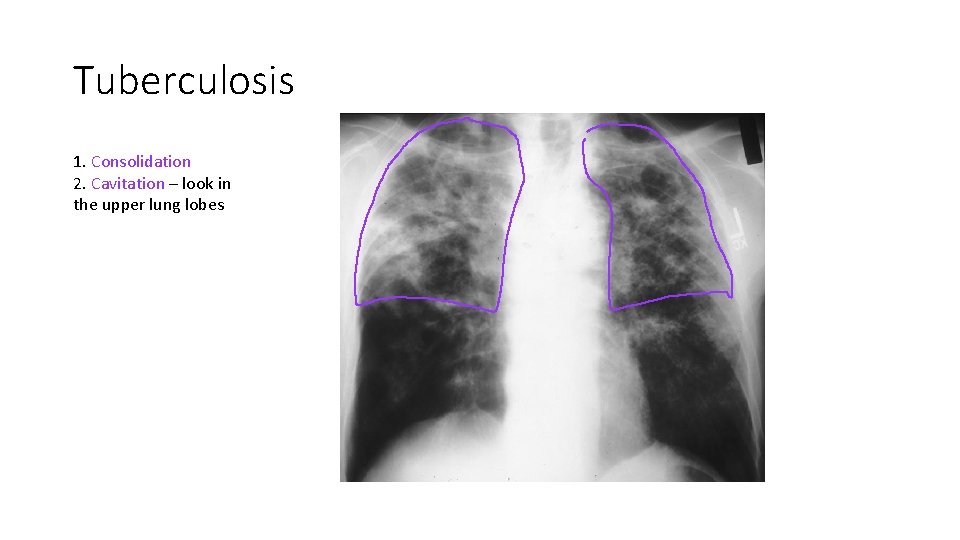

Tuberculosis 1. Consolidation 2. Cavitation – look in the upper lung lobes